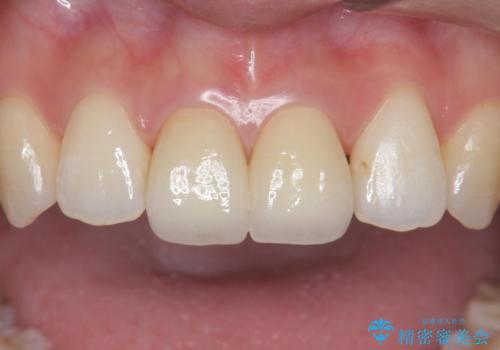

前歯には審美性も適合も良いクラウンを装着。

歯ぐきの状態も非常に良いです。

歯のがたつきも改善され、大変喜んでいただけました。